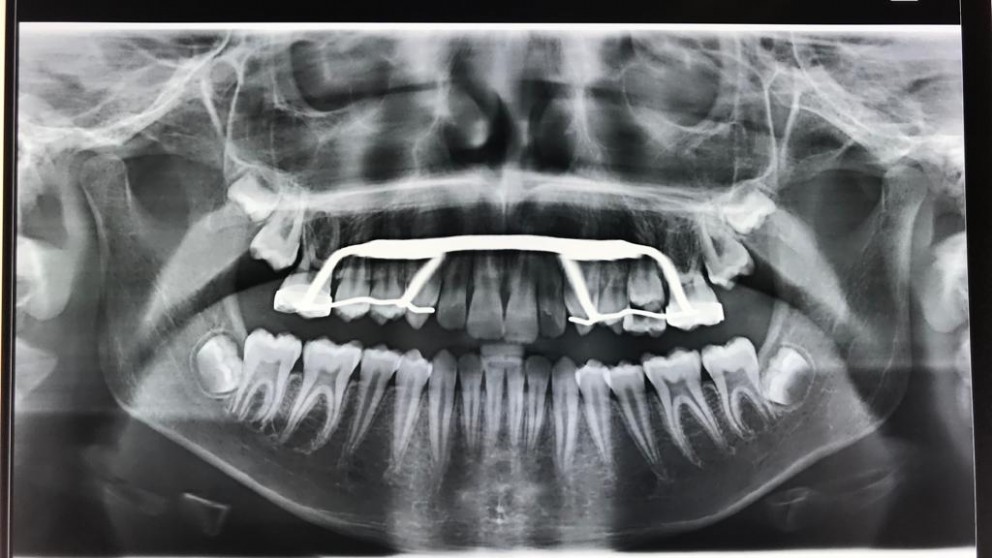

L'espansore è un dispositivo ortodontico usato per correggere il difetto del palato stretto. Viene fissato sui secondi premolari da latte o sui primi molari permanenti tramite una vite centrale che deve essere regolarmente attivata con una chiavetta per un periodo stabilito dall'ortodontista. Ha la funzione di espandere e allargare il palato.

Il palato stretto è uno dei disturbi più comuni che si riscontra nei bambini e consiste nella mancanza di spazio adeguato per far uscire in posizione corretta i denti permanenti. Ciò provoca un sovraffollamento dentale. Lo sapevi già?!